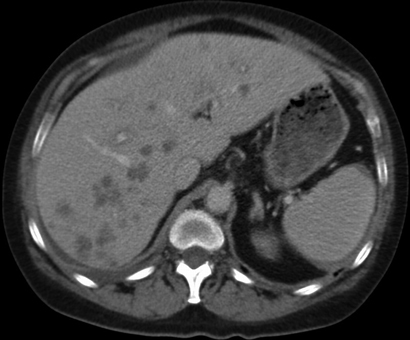

A 51-year-old woman was referred to hospital after an incidental finding of abnormal liver function test results (γ-glutamyl transpeptidase, 271 U/L [reference interval (RI), < 60 U/L]; alkaline phosphatase, 220 U/L [RI, 30–110 U/L]; hepatic transaminases, normal), acute renal impairment (urea, 11.7 mmol/L [RI, 2.7–8.0 mmol/L]; creatinine, 207 µmol/L [RI, 50–100 µmol/L]) and elevated globulin levels of 44 g/L (RI, 21–41 g/L). She was otherwise well and asymptomatic. Her past medical history included resistant hypertension with renal denervation 8 months earlier, and chronic macrocytic anaemia secondary to alcohol. Physical examination was largely unremarkable apart from several skin nodules and hepatomegaly (4 cm below the costal margin). She underwent an abdominal ultrasound, which showed multiple hypoechoic liver lesions suspicious for metastasis. An abdominal computed tomography (CT) scan (Box 1) confirmed the presence of hypovascular liver lesions suggestive of metastasis. Malignancy screening, including mammography, colonoscopy and CT of the chest, abdomen and pelvis, was negative. A subsequent liver biopsy specimen showed necrotising granulomas with no evidence of malignancy. The initial histopathological impression was of mycobacterial infection, despite negative Ziehl–Neelsen and Gram stains and the absence of infective organisms.

Histological changes of NXG are prominent in the skin, but some features have been observed in visceral organs. Although associated hepatomegaly has been observed,2 histological examination of the liver has only been reported in a few cases — two patients showed reactive changes including nodular transformation,4,6 and one showed amyloidosis.7 Syncytial giant cell hepatitis was reported in a patient with NXG, but there was no more than a tenuous association.8 Our patient's liver biopsy specimen (Box 3, D) showed necrobiosis and necrosis associated with diffuse granulomatous infiltrate similar to that seen in the skin specimens. As NXG can lead to necrobiotic granulomatous inflammation in other organs, it is reasonable to expect that similar infiltrate may occur within the liver. We believe this is the first reported case of true liver involvement of NXG.